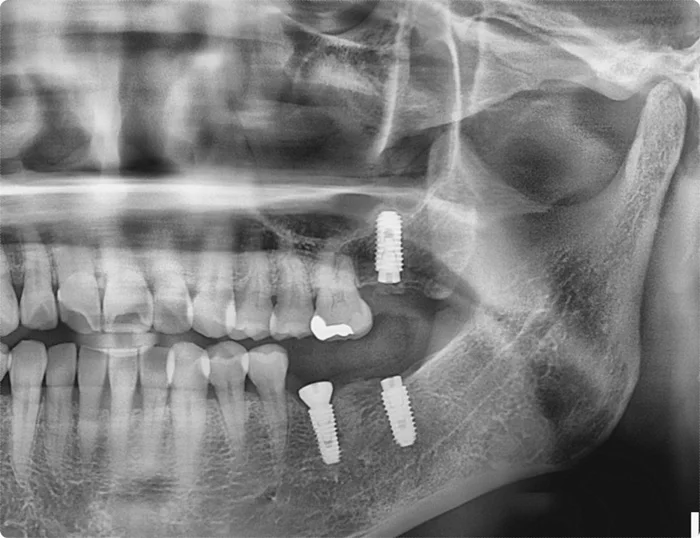

오산 임플란트파절 꼭 연결해야 하는건가요? 안녕하세요. 서울버팀치과 원장 엄용국입니다. 가끔 환자분들께서 “임플란트는 서로 붙이지 말고 각각 따로 해주세요”라고 말씀하시곤 합니다. 보통은 치아 하나당 하나의 보철물을 제작해 개별적으로 식립하는 방식이 많이...

오산 임플란트 파절 (4)